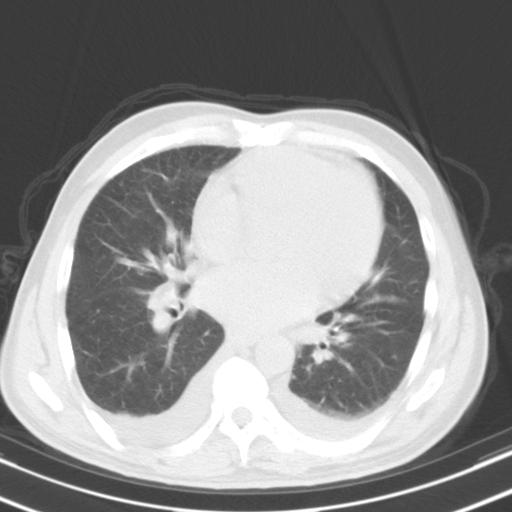

以下是引用zjzjr在2010-3-21 17:39:00的发言:[br]右下中心型肺癌并阻塞性肺炎/不张,纵膈淋巴结肿大,右侧大量胸腔积液,左侧少量胸腔积液

以下是引用zxl51642在2010-3-21 17:06:00的发言:[br]右下中心型肺癌并阻塞性肺炎/不张,纵膈淋巴结肿大,右侧大量胸腔积液,左侧少量胸腔积液,少量腹水。建议纤维支气管镜进一步检查。